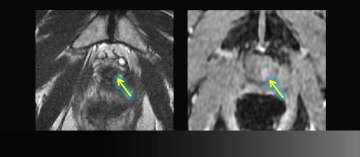

6) Dynamic Contrast-Enhancement for Biochemical Failure

Dynamic Contrast-Enhancement for Biochemical Failure